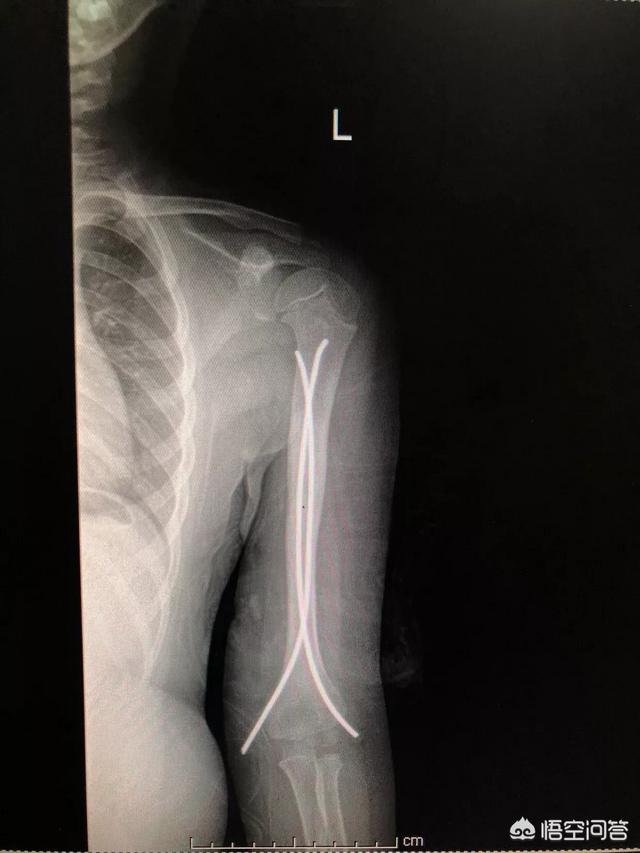

如果骨折移位错位很明显的话那就要选择手术治疗。手术方式远近端可用克氏针+石膏托治疗 ,如果是肱骨干骨折有弹性髓内钉内固定。也有钢板内固定,可以根据具体情况来决定。弹性髓内钉手术治疗是很微创的。术后疤痕也小。如果是接近成年的小孩的话,那可能就要做切开复位钢板内固定,这样的话,之后可能会有疤痕。可以根据具体情况来决定。